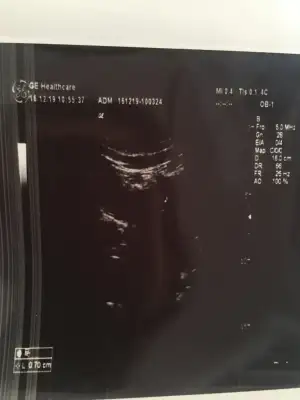

kac haftalik bilmiorum ama beta hcg 900-1000 arasi.karindan bakilan ultrasonda kese oldugu dusunuluyor

IMG_20191216_102203.webp